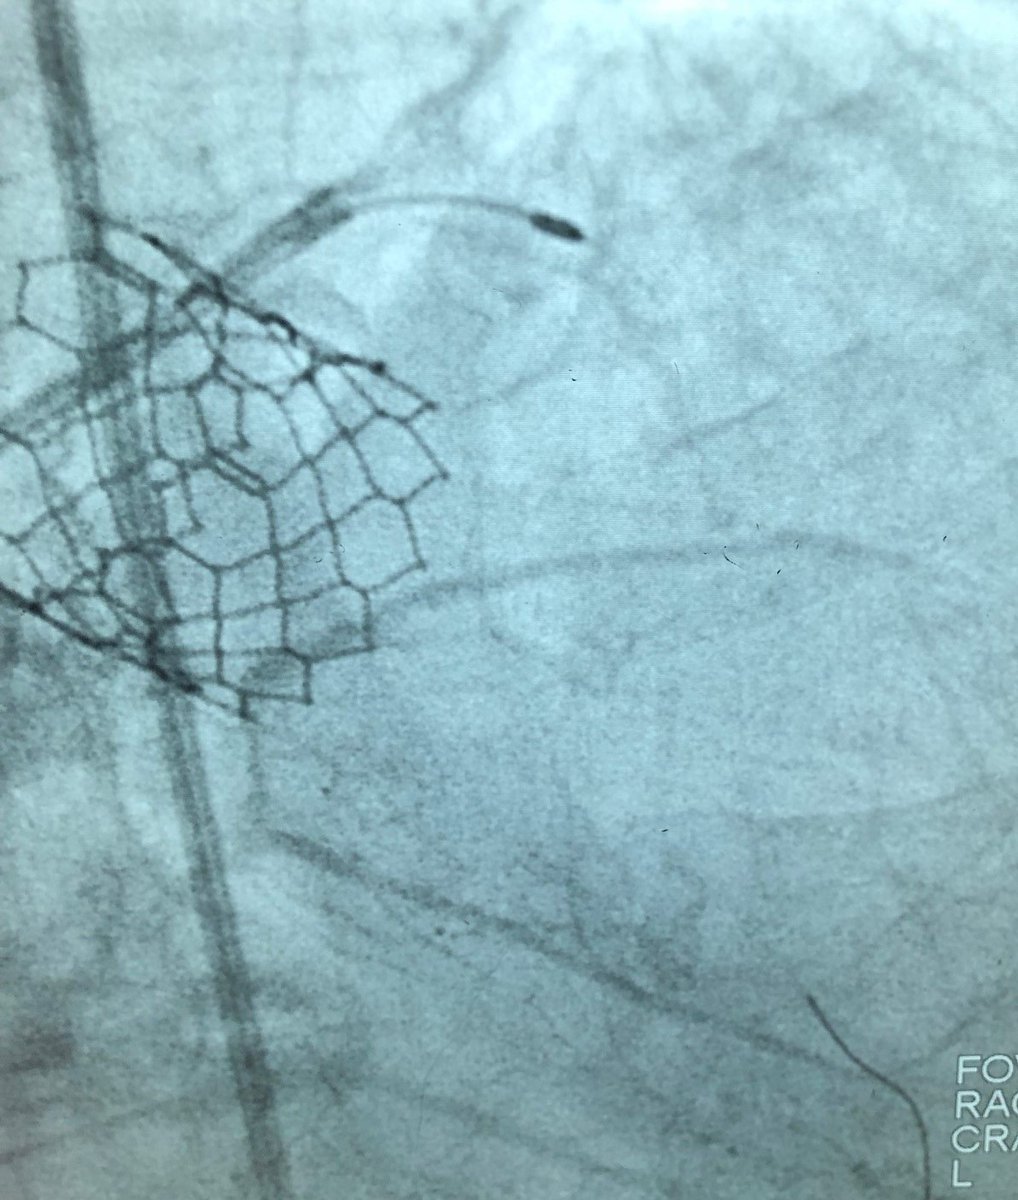

Dr. @KPohlel of @PiedmontHealth Athens Regional faced an unyielding LAD. Unable to cross the lesion the prior day, he switched to the #RotaShock technique, crossing the lesion with a 1.75 rota burr and then cracking the calcium with 4.0 #ShockwaveC2. ISI bit.ly/3iEq7fC

ShockwaveIVL's tweet image. Dr. @KPohlel of @PiedmontHealth Athens Regional faced an unyielding LAD. Unable to cross the lesion the prior day, he switched to the #RotaShock technique, crossing the lesion with a 1.75 rota burr and then cracking the calcium with 4.0 #ShockwaveC2.